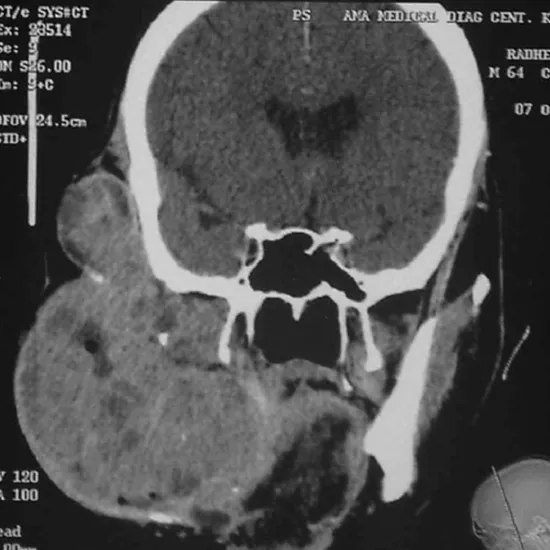

CECT-Face is a contrast-enhanced computed tomography imaging technique used to visualise the bones and soft tissue structures of the face. It gives a clear picture of the dense and soft tissues such as the facial bones, air-filled hollow sinuses, throat, salivary glands, and so on. Any abnormality, such as a clog, tumour, or inflammation, can thus be identified and personalised treatment can begin immediately.

A contrast dye is injected into your body during this procedure to highlight the differences between the structures. The doughnut-shaped tube emits powerful X-rays that rotate around your face, capturing 3-D images that are displayed on a monitor. You may experience slight burning at the injection site, a metallic taste, and warm flushing, which should go away after a few seconds.